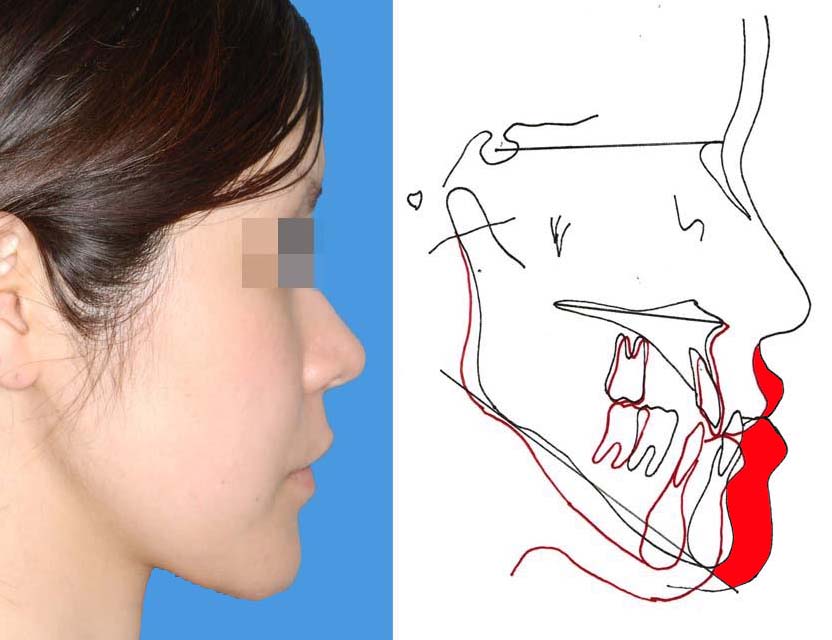

品質一番の 下顎前突(反対咬合) 奈良市の矯正歯科「氏井矯正歯科 | 歯科学